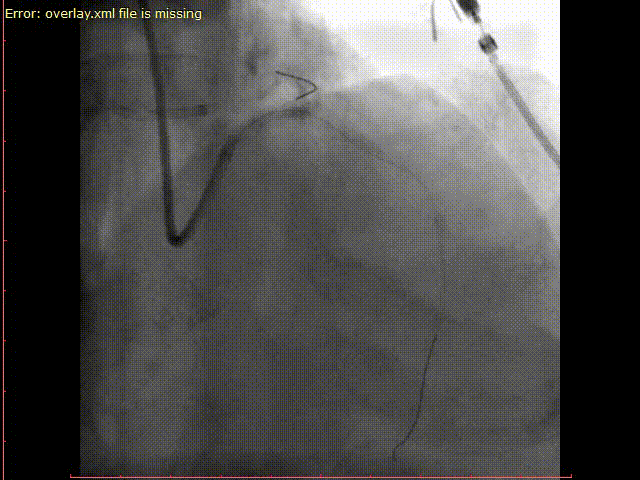

图15-2. 用3.0*12mm nc球囊以12~20个大气压扩张前降支支架,用4.